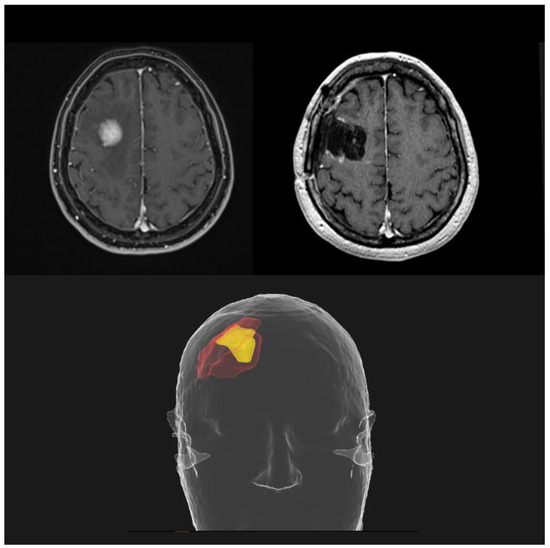

3.1. Adjuvant SRS

3.2. Neoadjuvant SRS